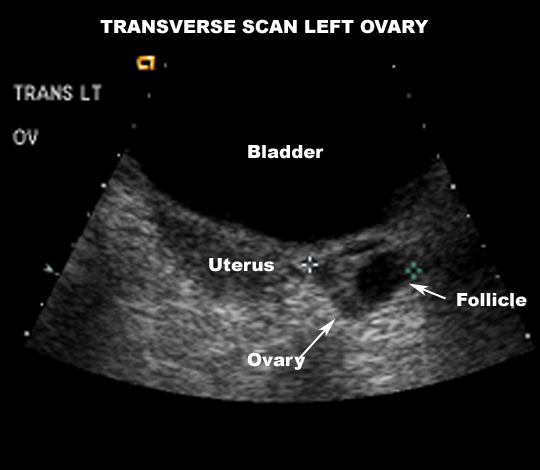

US Pelvis |